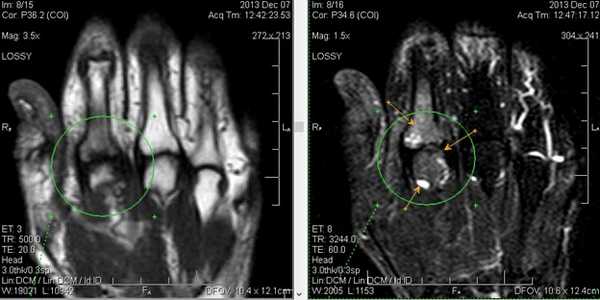

Клинические проявления у пациента: боль и ограничение движений после падения на вытянутую руку 4 месяца назад.

Перелом ладьевидной кости с явлениями асептического некроза проксимального полюса и, связанного с ним, остеоартрита. Ладьевидный перелом обычно происходит из-за падения на вытянутую руку, которое приводит к гиперэкстензии лучезапястного сустава.

Аваскулярный (асептический) некроз нередко сопутствует переломам проксимальной части ладьевидной и переломам полулунной кости, а также неадекватно репонированным и иммобилизированным переломам этих костей. Основная причина - нарушение трофики участка кости при повреждении питающих артерий.

Методом выбора в диагностике и стадировании остеонекроза костей кисти является МРТ.